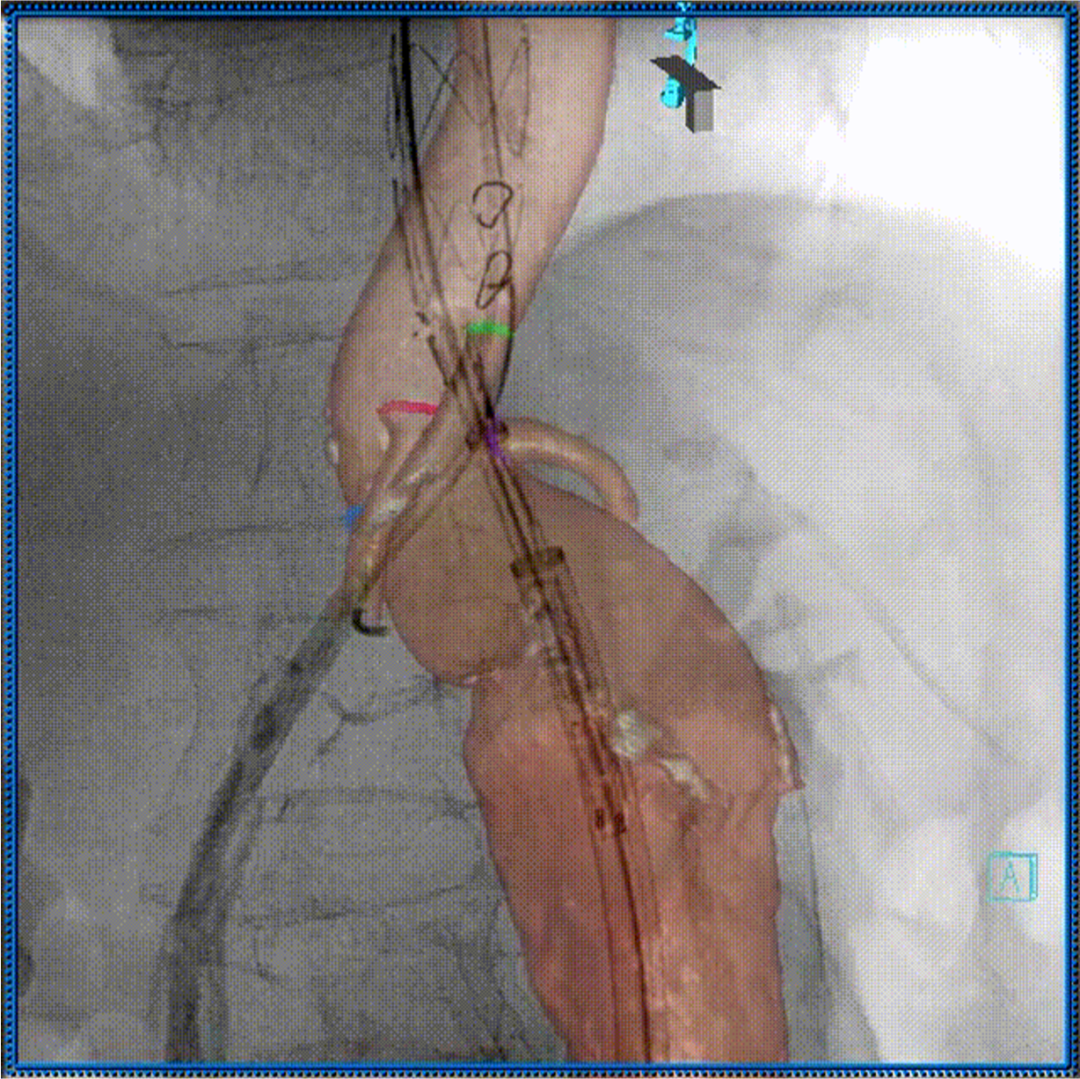

3D影像引导下完成窗口超选、置管及确认

肠系膜上动脉重建

左肾动脉重建

右肾动脉重建

四分支重建后造影,各分支血流通畅